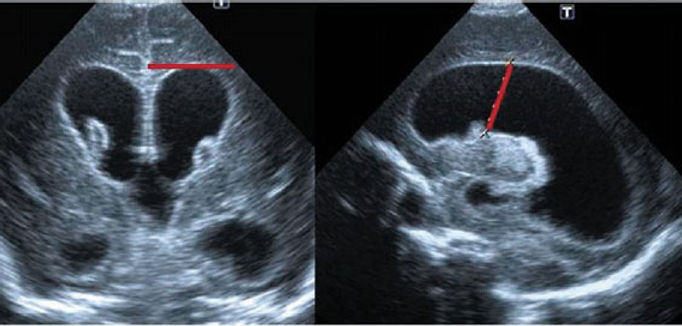

Con esta técnica se puede ver lo que hay dentro del cráneo. Con la sonda de ecografía adecuada y a través de las fontanelas se pueden ver y estudiar el cerebro y sus arterias, el cerebelo y el resto de órganos que hay dentro de la cavidad craneal. También es posible ver algunas de las enfermedades que pueden existir en esta parte del cuerpo.

También nos sirve para ver otras enfermedades como tumores, malformaciones e incluso infartos o trombos dentro de las arterias.